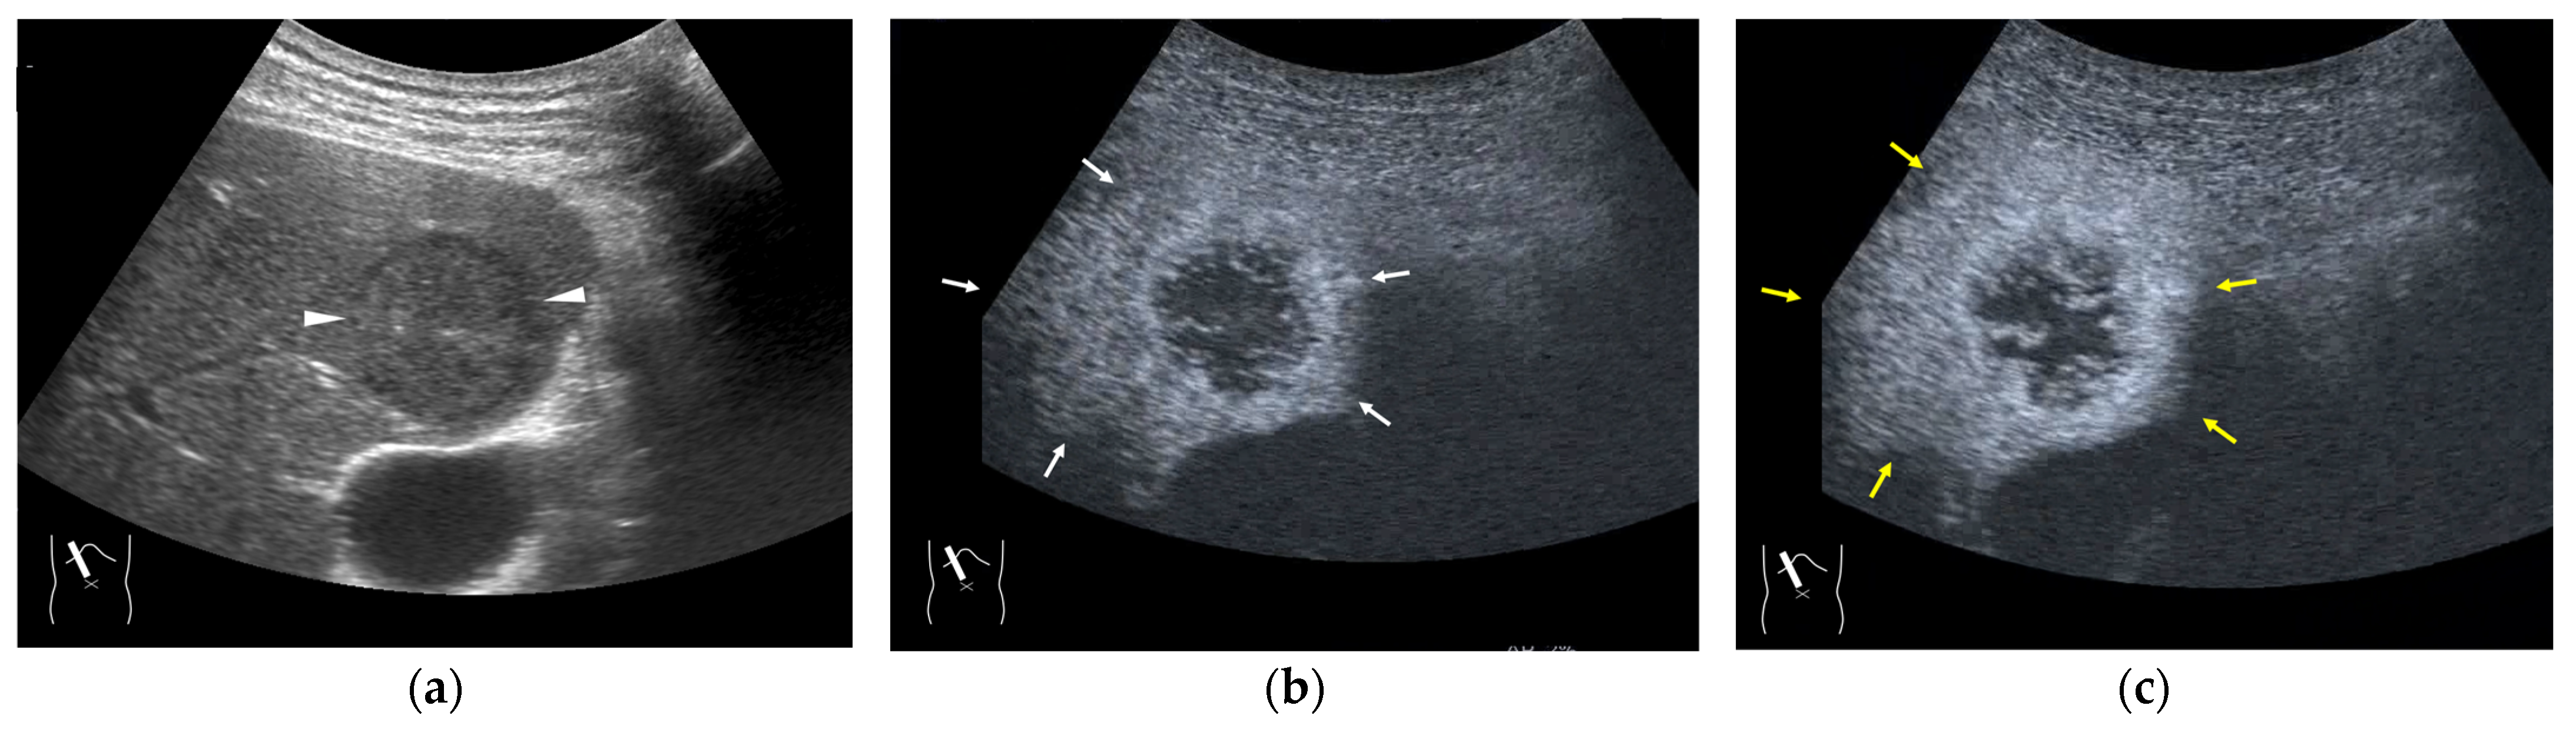

3.1. Hepatocellular Carcinoma (HCC)

3.2. Liver Metastasis

3.3. Benign Liver Tumors